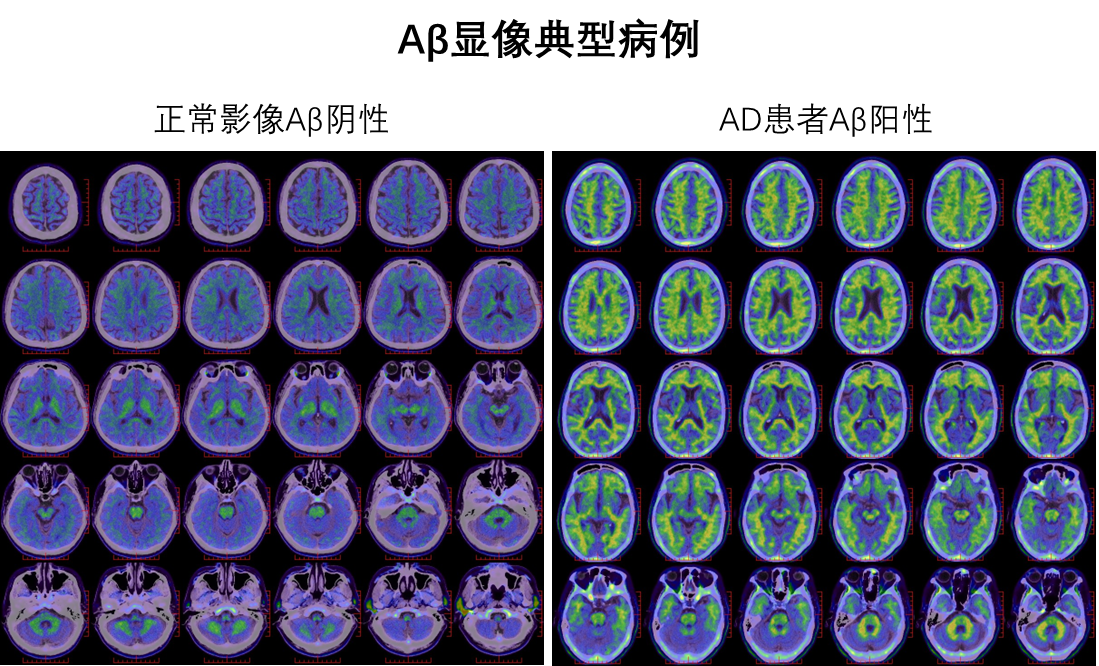

Aβ显像主要用于检测大脑中是否堆积了“淀粉样蛋白”。淀粉样蛋白的堆积是阿尔茨海默病的典型标志之一,通过Aβ显像,医生可以直观地观察到大脑中淀粉样蛋白的分布情况,从而为阿尔茨海默病的早期诊断提供重要依据。